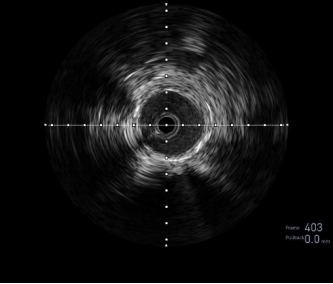

图:DA 造影+通过病变

图:IVUS确认

图:Hawk Plus 切除斑块

图:IN.PACT DCB 6-250 扩张,最终造影